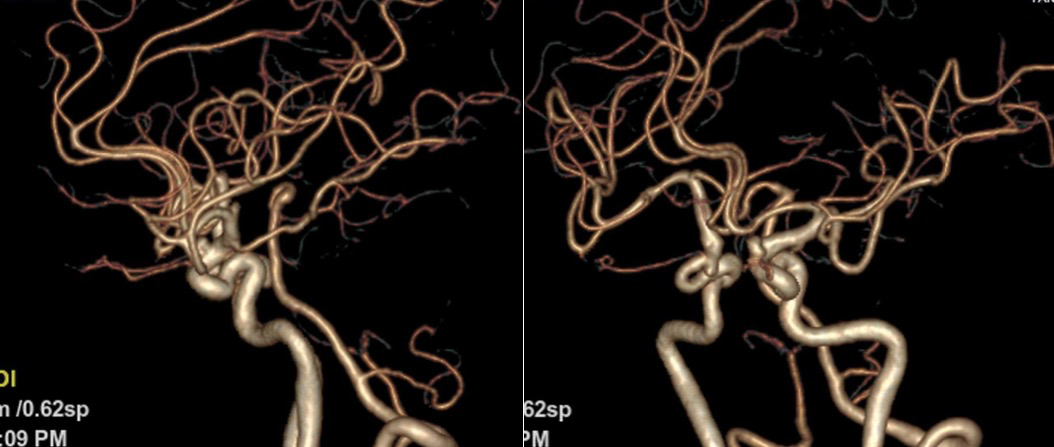

图2 头颅CTA(2019-12-30)

患者2019-12-14突发右侧肢体活动不利,表现为右手持物困难,右下肢尚可行走,伴有吞咽困难、饮水呛咳,就诊于我院行头颅核磁检查提示左侧内囊后肢急性脑梗死,于我院住院治疗后病情好转,住院期间完善头颅核磁提示双侧颈内动脉动脉瘤可能,进一步完善CTA提示双侧颈内动脉眼动脉段动脉瘤,患者为进一步治疗以“颅内动脉瘤”入院。

1. 该患者为双侧颈内动脉多发动脉瘤,合并高血压等危险因素,右侧颈内动脉可见多发小动脉瘤,左侧颈内动脉动脉瘤瘤体较大,不规则,破裂风险较高,这是我们选择左侧颈内动脉动脉瘤介入治疗的指征。